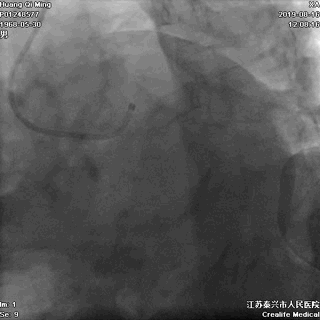

冠状动脉造影

右冠状动脉无严重狭窄

左主干前分叉处血管正常

LCX近中段病变,狭窄最重达90%

LAD中远段血管偏细,弥漫性病变,狭窄达90%